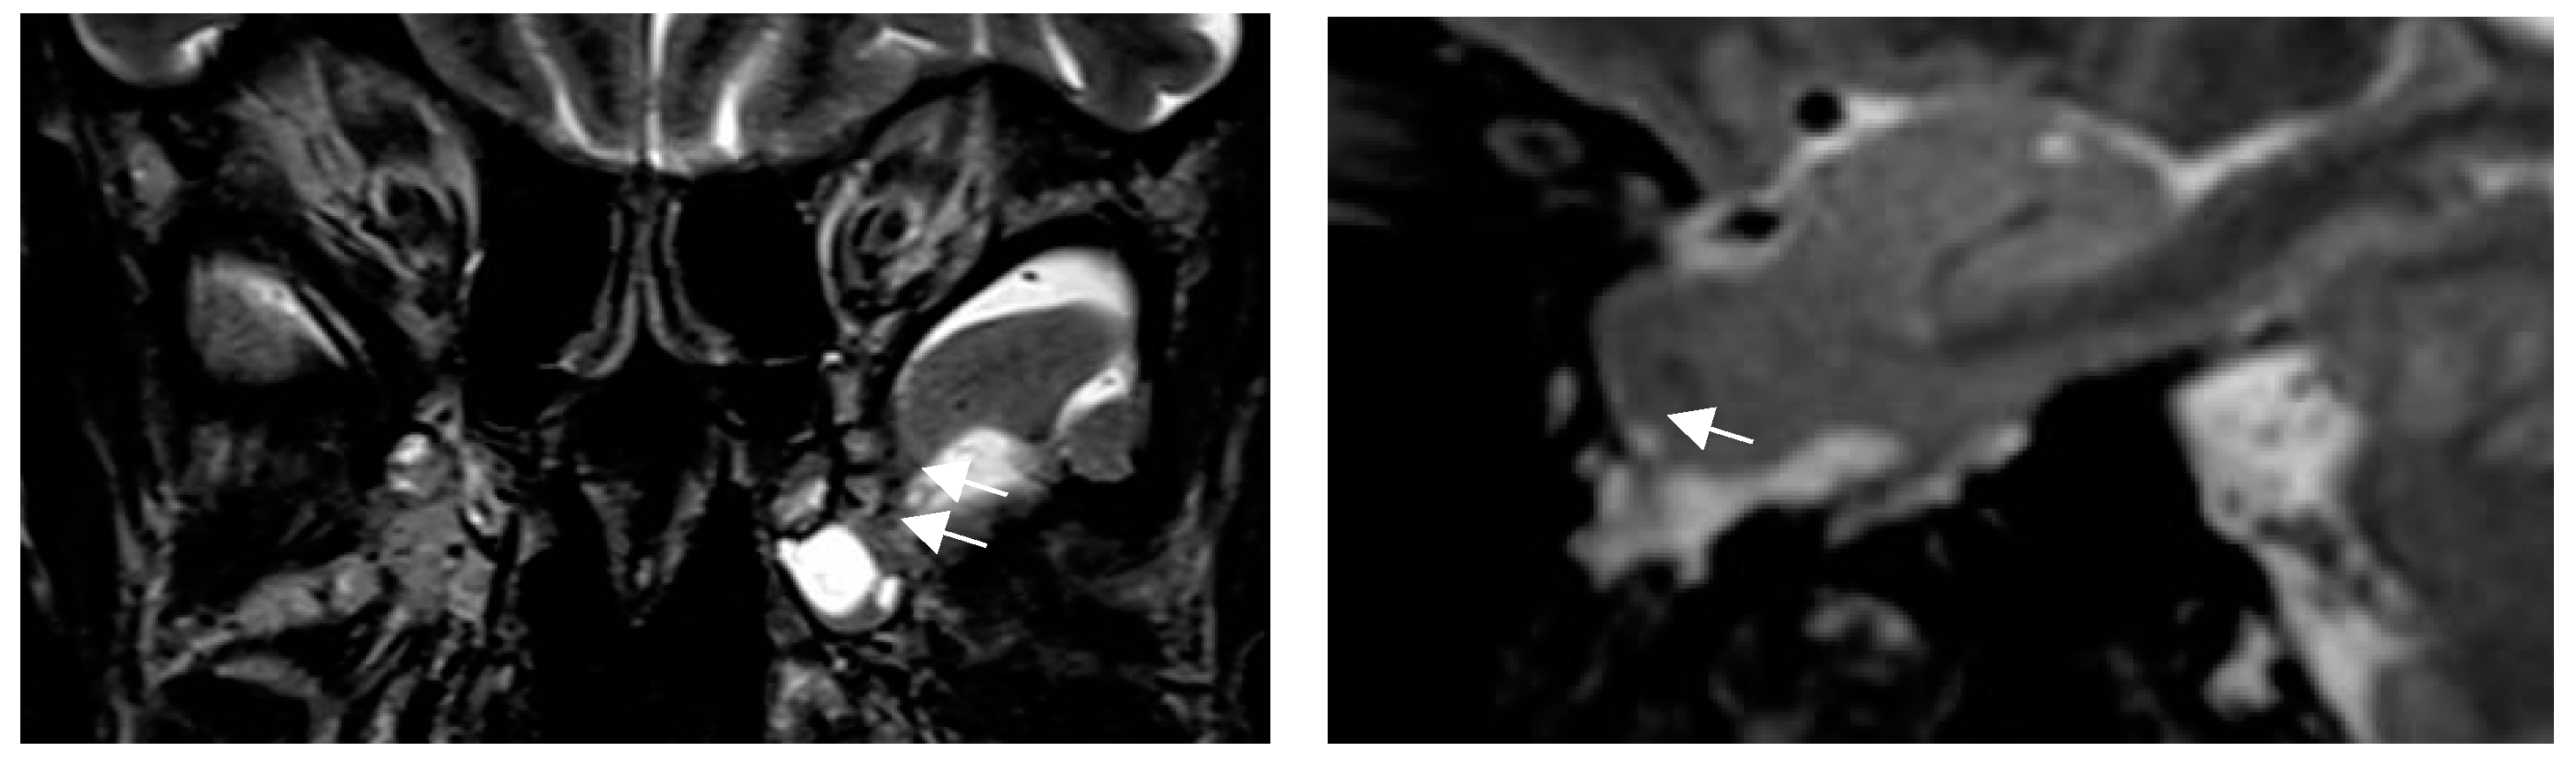

4.5. New MR Sequences Display Tissue Properties for Improved Visualization of Lesions

4.7. Postprocessing by Quantitative Analysis of Signal Intensity, Volumetry Enhances Temporal Lesion Identification

- Coan AC Morita ME, de Campos DM, Yassuda CL, Cendes F. Amygdala enlargement in patients with mesial temporal lobe epilepsy without hippocampal sclerosis. Front Neurol. 2013;4:166-170.

- Coan AC, Kubota B, Bergo FPG, Campos BM, Cende F. 3T MRI Quantification of Hippocampal Volume and Signal in Mesial Temporal Lobe Epilepsy Improves Detection of Hippocampal Sclerosis AJNR 2014; 35:77–88.